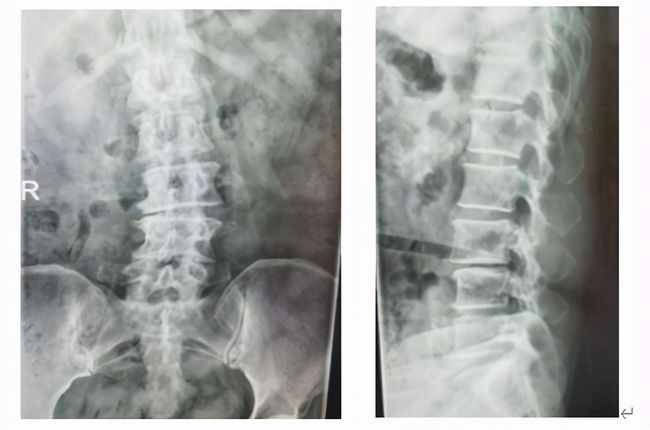

近期,邵女士前往上海交通大学医学院附属同仁医院脊柱外科就医,X线检查,腰4椎体轻度滑脱并有退变性侧弯,MR检查提示椎间盘突出,椎管明显狭窄,黄韧带肥厚、硬膜囊及神经根受压,诊断为:腰椎滑脱伴椎管狭窄症。